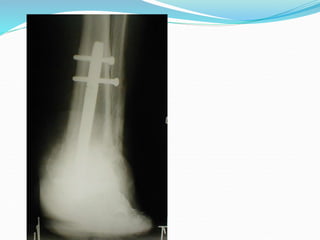

Case 4

Charcot Foot